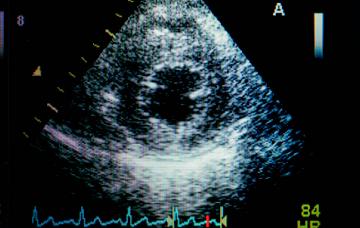

Diagnóstico de la insuficiencia mitral

El principal método para detectar insuficiencia mitral es la ecocardiografía, que permite establecer el diagnóstico e identificar sus causas.